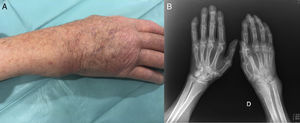

Se realiza exploración ecográfica (Esaote MyLab 70®) diagnóstica en escala de grises, que demuestra una colección redondeada, delimitada y desplazable, que se extiende de modo heterogéneo en los 6 compartimentos del mecanismo extensor de la muñeca (fig. 2A), que al ser evaluada mediante color Doppler presenta un G3, sugiriendo un proceso inflamatorio-infeccioso activo (fig. 2B y C). Se realiza una punción eco-guiada de la que se extraen 5cc de líquido turbio que, en la tinción de Gram directa presenta abundantes leucocitos, ningún microorganismo y el cultivo aerobio resulta negativo. En la tinción de Ziehl-Neelsen tampoco se observan bacilos ácido-alcohol resistentes. Sin embargo a 37 grados en cultivo de Lowenstein-Jensen, a los 9 días se confirma la existencia de Mycobacterium tuberculosis (M. tuberculosis). Se realiza Rx de tórax: ICT>0,5, cerclaje esternal, mínimo pinzamiento posterior de seno costofrénico, aumento de la densidad apical derecha y se inicia tratamiento tuberculostático con 5 fármacos (Rimstar® 5 comprimidos/día, junto a vitamina B6 oral/semanal, durante 9 meses), para tratar su monoartritis infecciosa por M. tuberculosis.

A) Imagen del compartimento dorsal de la muñeca derecha. Distorsión de la arquitectura de los compartimentos extensores. Presencia de una gran masa de partes blandas que deforma el recorrido de los extensores comunes, del extensor del quinto dedo y del extensor cubital. B) Imagen en corte longitudinal, y C) Transversal del tendón extensor común de los dedos a nivel de la muñeca. Incremento de neo-vascularización con señal color Doppler evidente (G3) de actividad sobre el tendón extensor e infiltración de material infeccioso alrededor.